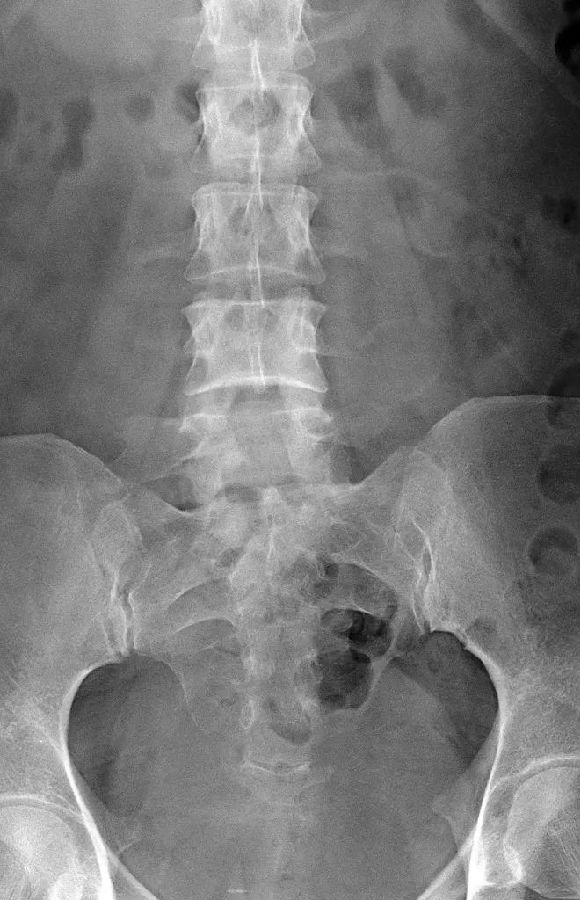

I型:主要为腰5横突发育不良,横突宽度大于19mm,并将其分为两个亚型Ia(单侧横突发育不良)或Ib(双侧横突发育不良)

L5右侧横突肥大,为Ⅰa型

L5双侧横突肥大,为Ⅰb型